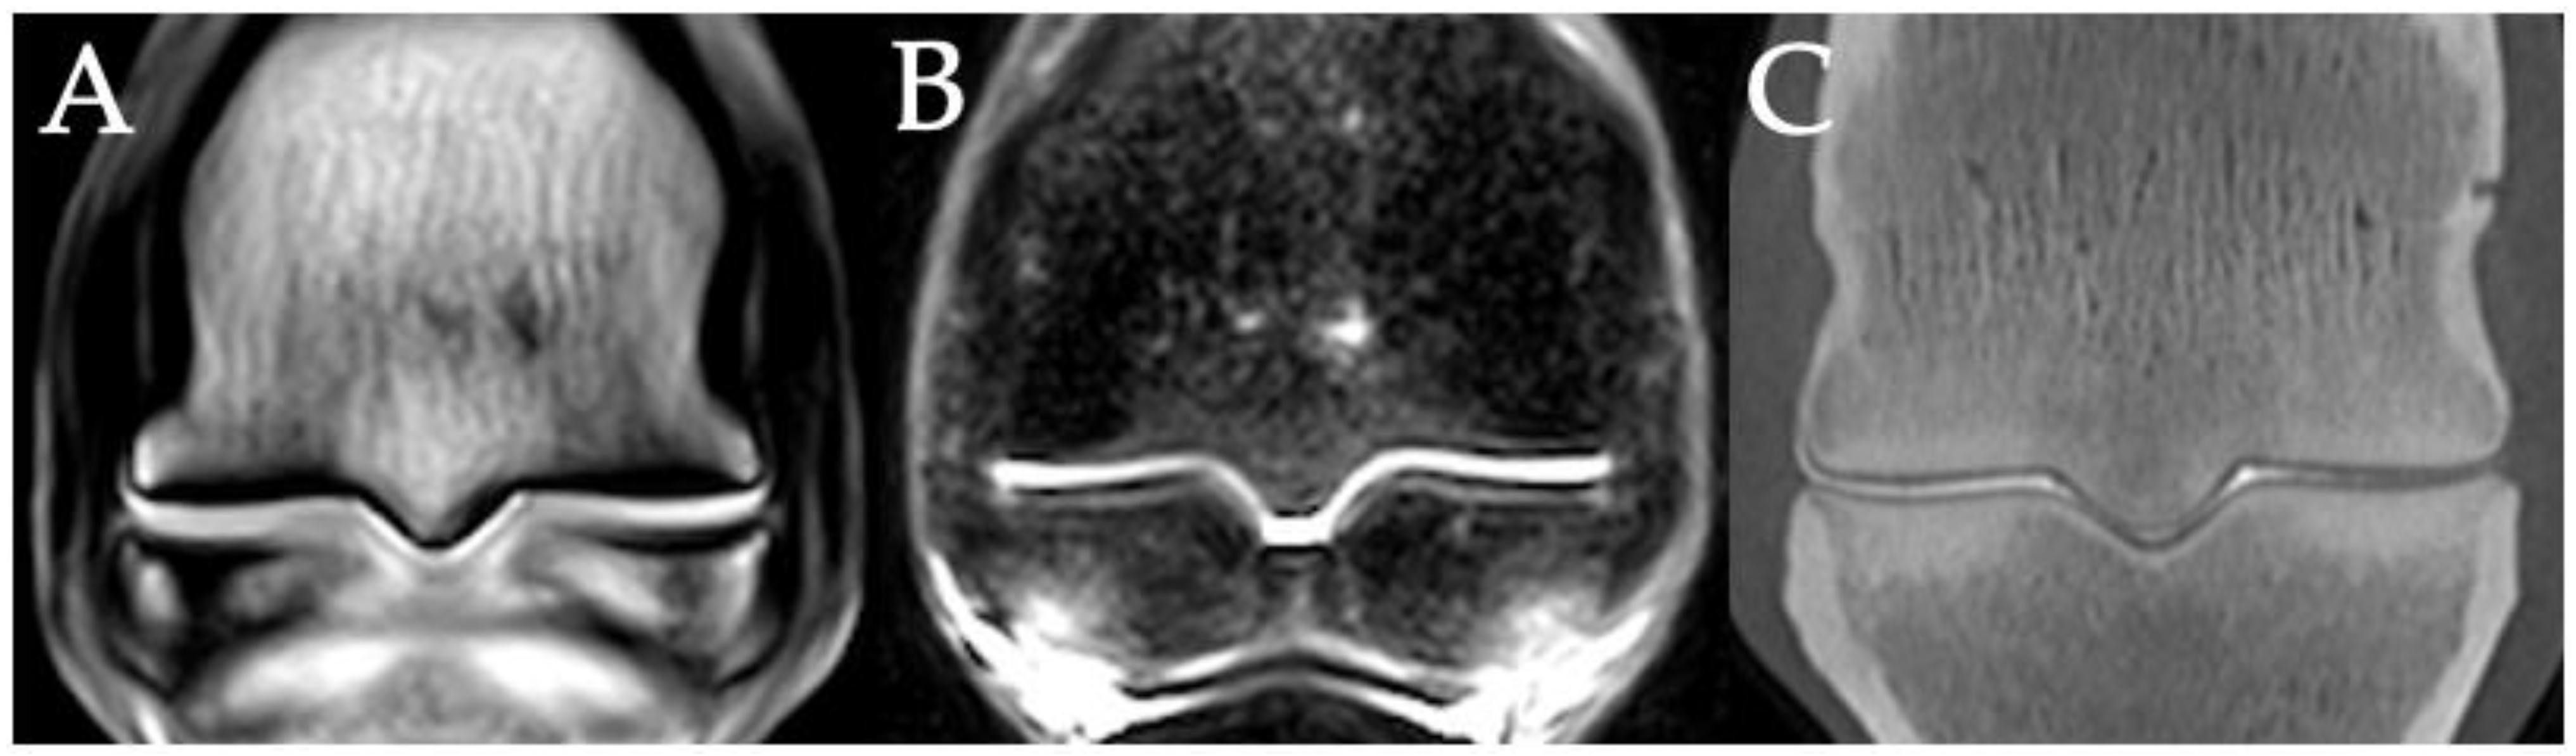

3.2. Sclerosis of the Subchondral and Adjacent Medullary Bone of the PSGs